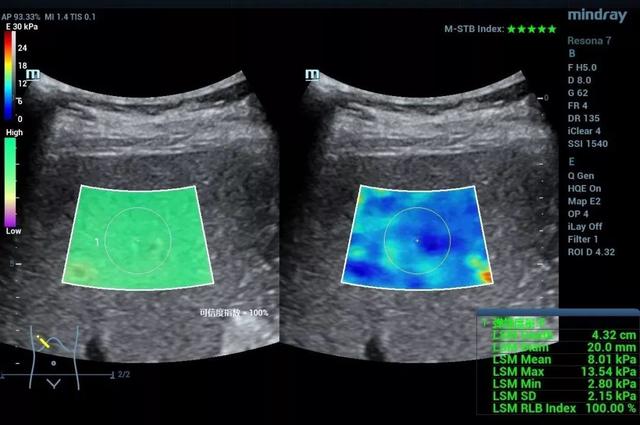

作为一种无创的能够反应组织硬度的功能性成像方法。目前剪切波弹性成像的研究已经涉及肝脏、甲状腺、乳腺、胃肠道、肌骨等方方面面,对于弥漫性病变的分级、局灶性病变的鉴别诊断、疾病的监测及随访等都有重要的意义。例如诊断肝脏纤维化的分期,从F1-F4的图像中,我们发现,尽管二维声像图差别不大,但当纤维化程度增高时,肝脏杨氏模量也增高了,也就是说肝脏“变硬”了。可见,超声发展到这里,不但有形态学上的灰阶超声,血流动力学上的彩色多普勒超声,还有机械力学上的弹性超声。

肝纤维化F2期

肝纤维化F3期